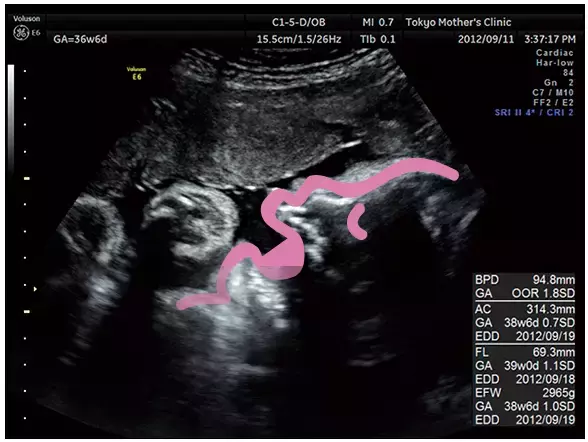

臨月になると体の一部しか見えません。成長の具合を最終チェックします。

この頃になるとエコー写真に写るのは体の一部だけ。大きな口を開けている横顔がくっきりと見えます。

写真提供:東京マザーズクリニック